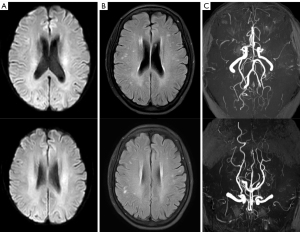

In recent years, the patient has been monitored with frequent MRI scans under the latest noninvasive clinically available MRI techniques, such as susceptibility-weighted imaging (SWI) and arterial spin labeling (ASL). Since 2013, ASL and other MRI sequences have been carried out as routine MRI examinations on a 3.0-Tesla MRI scanner (Ingenia, Philips, Amsterdam, The Netherlands) with 16-channel head coils. Multiple brain MRIs have shown nonprogressive small white matter ischemic foci (Figure 3A), while SWI has revealed no associated microhemorrhage (Figure 3B). TOF-MRA has consistently shown the presence of collaterals from bilateral PCAs and vertebrobasilar arteries (Figure 3C).